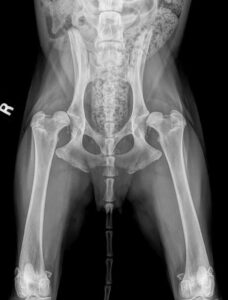

2. Radiographs (X-rays): This is the definitive diagnostic tool. Your dog will be sedated or anesthetized to get clear, stress-free views of the hip joints. The vet will look for signs like a shallow socket, flattened femoral head, osteoarthritis (bone spurs), and joint incongruity.

3. Grading: Hip dysplasia is typically graded on a scale (like the OFA or PennHIP systems). Understanding the grade helps determine prognosis and treatment.